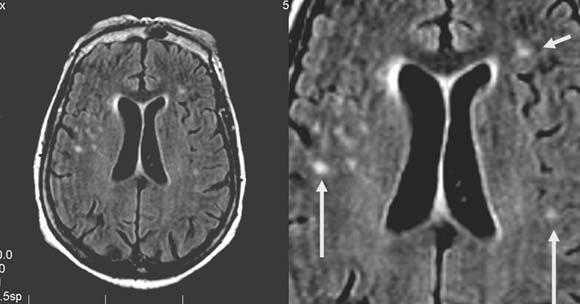

Церебральная гемиатрофия (Dyke-Davidoff-Masson syndrome)

Анамнез: Юноша, 18 лет. Когнитивные нарушения, левосторонний гемипарез с раннего детства. Два эпизода судорог за последние две недели.

Описание исследования Атрофия правого полушария головного мозга с энцефаломаляцией и глиозом в смежных отделах лобной, теменной и височной долей (бассейн правой СМА), exvacuo-дилатация правого бокового желудочка, атрофия ипсилатеральной ножки мозга, базальных ганглиев и таламуса, легкая перекрестная атрофия мозжечка (левая гемисфера), ипсилатеральное смещение срединных структур и некоторое утолщение костей свода черепа.